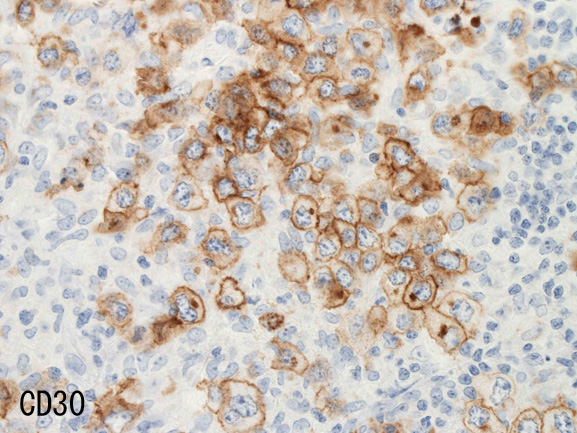

• CD30は50%に陽性。CD15は陰性。

腫瘍細胞はCD20+, CD30+, CD15-, PAX-5+, Oct.2+, BOB.1+(Oct2, BOB1は田丸先生の染色結果), EBER-ISH+, EBNA2-